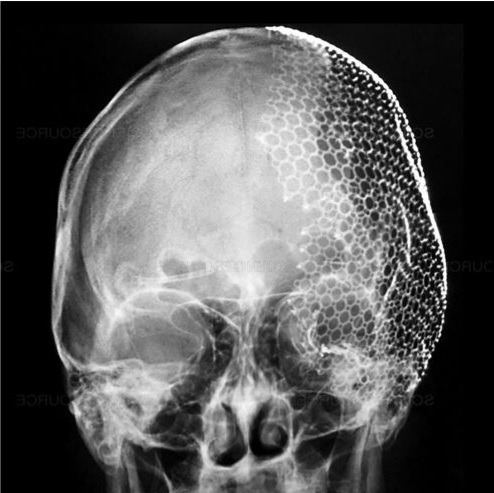

Công nghệ in 3D trong ghép mảnh sọ Titanium

Việc tạo hình chính xác khuyết hổng xương sọ luôn là thách thức lớn. Nếu tạo hình không phù hợp, mảnh ghép có thể bị lệch, cong vênh và không khớp với hộp sọ.

Công nghệ in 3D đã giải quyết vấn đề này bằng cách:

- Chụp CT đa dãy để tạo dữ liệu 3D vùng khuyết sọ

- Xử lý dữ liệu để thiết kế mảnh ghép theo đúng hình dạng thực tế

- Sản xuất mảnh ghép bằng vật liệu phù hợp (Titanium, PEEK, xi măng sinh học…)

Nhờ đó, mảnh ghép:

- Khớp chính xác với cấu trúc hộp sọ

- Đảm bảo tính thẩm mỹ cao

- Tăng hiệu quả điều trị

Hiện nay, Trung tâm Kỹ thuật cao phối hợp với Khoa Phẫu thuật Thần kinh – Bệnh viện Đa khoa Xanh Pôn đã triển khai thường quy kỹ thuật này, đặc biệt là ghép mảnh sọ 3D Titanium, mang lại kết quả an toàn và tối ưu thẩm mỹ.